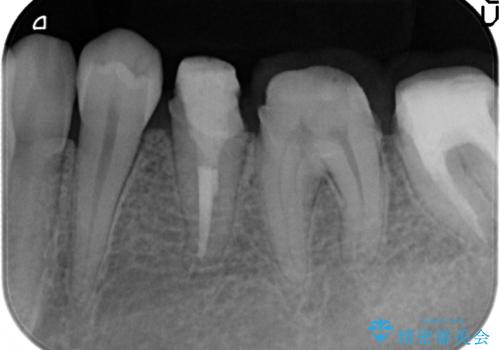

- 左下の歯が虫歯により崩壊し、歯ぐきからの出血も毎回歯ブラシを行う際に出ることから治療を求めて来院されました。

現在装着されているクラウンを除去したところ、クラウンマージンが歯肉縁下となり歯ぐきの炎症が認められたため再度オールセラミッククラウンを製作する前に歯周外科手術を行い歯ぐきの状態を改善しました。